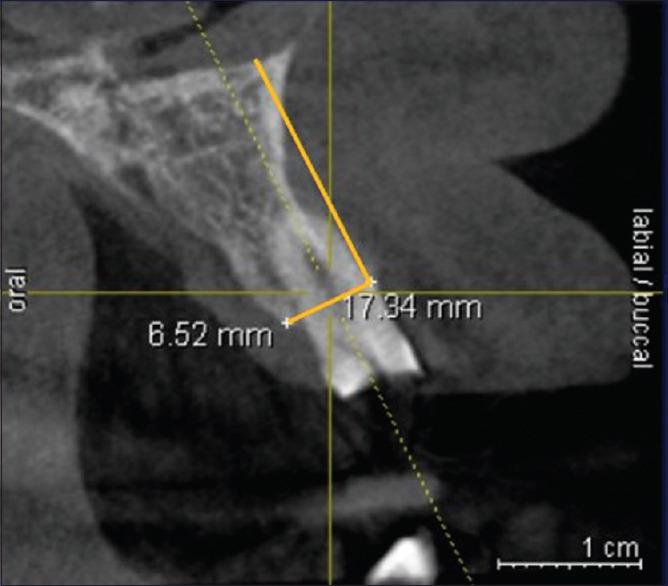

MATERIALS AND METHODS

Twenty-six sites, i.e., 13 sites requiring partial tooth extraction (test sites) and 13 sites with whole tooth extraction (control sites), in the maxillary anterior region were included. In each patient, at least two sites were included (one test and one control). After both procedures, a collagen sponge was placed in the socket and sutured with silk suture. The height of the labial crestal bone and width of the socket at both sites were evaluated by the cone-beam computed tomography examination preoperatively at baseline and after a 3-month follow-up period.

纳入上颌前部区域的26个位点,即13个需要部分拔牙的位点(试验位点)和13个全牙拔除的位点(对照位点)。每位患者至少纳入两个位点(一个试验位点和一个对照位点)。两种操作后,在牙槽窝内放置胶原海绵并用丝线缝合。通过锥形束计算机断层扫描检查在术前基线以及3个月随访期后评估两个位点的唇侧牙槽嵴骨高度和牙槽窝宽度。